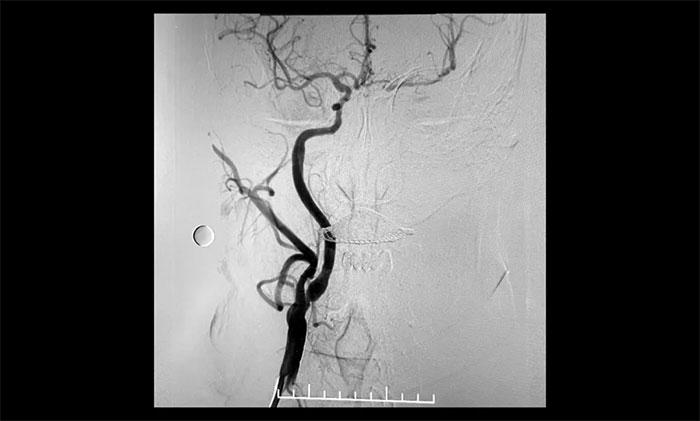

經(jīng)微導絲成功進入狹窄、閉塞頸內(nèi)動脈,在支架保護下,進行球囊逐段擴張,支架置入……,經(jīng)多次球囊擴張,置入支架后,造影顯示左頸內(nèi)動脈起始段狹窄明顯改善,左頸內(nèi)動脈顱內(nèi)段順利再通,左頸內(nèi)動脈眼動脈段、后交通段狹窄明顯改善。造影及3D造影見左頸總動脈、左頸內(nèi)動脈、左大腦中動脈顯影可,行支架CT見顱內(nèi)支架成形可,手術取得成功!

▲ 術后,右頸內(nèi)動脈起始段狹窄明顯改善

▲術后,左頸內(nèi)動脈起始段狹窄明顯改善,左頸內(nèi)動脈顱內(nèi)段順利再通,左頸內(nèi)動脈眼動脈段、后交通段狹窄明顯改善